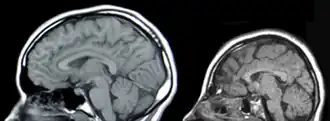

Resonancia Magnética de la Cabeza, Izquierda: Normal, Derecha:Microcefalia. | ||

La microcefalia es un trastorno neurológico en el que la circunferencia de la cabeza es más pequeña que la circunferencia promedio para la edad y el sexo del niño. Se define como una circunferencia de cabeza más de dos desviaciones típicas menos de lo normal según el sexo y la edad.[1][2] Algunos académicos la definen como tres desviaciones en la circunferencia de la cabeza.[3] La microcefalia puede ser congénita o puede producirse en los primeros años de vida. El trastorno puede provenir de una amplia variedad de enfermedades que provocan un crecimiento alterado del cerebro o de síndromes relacionados con alteraciones cromosómicas. Se sospecha que la fiebre del Zika causa microcefalia.[4][5][6]